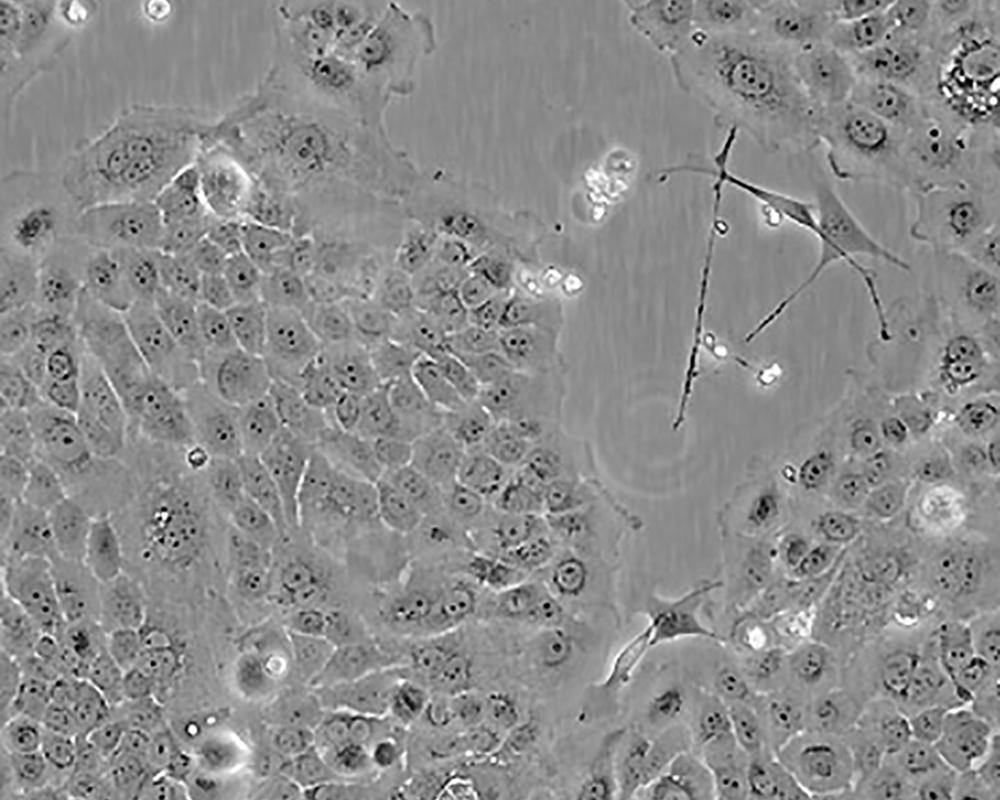

BxPC-3(BxPC3)

產(chǎn)品名稱 BxPC-3(BxPC3)

中文名稱 人原位胰腺腺癌細(xì)胞

組織來(lái)源 胰腺導(dǎo)管腺癌;女性

生長(zhǎng)特性 adherent

形態(tài)特征 epithelial

細(xì)胞描述 The cells do not express the cystic fibrosis transmembrane conductance regulator(CFTR). A CFTR positive pancreatic line, Capan-1 is available.